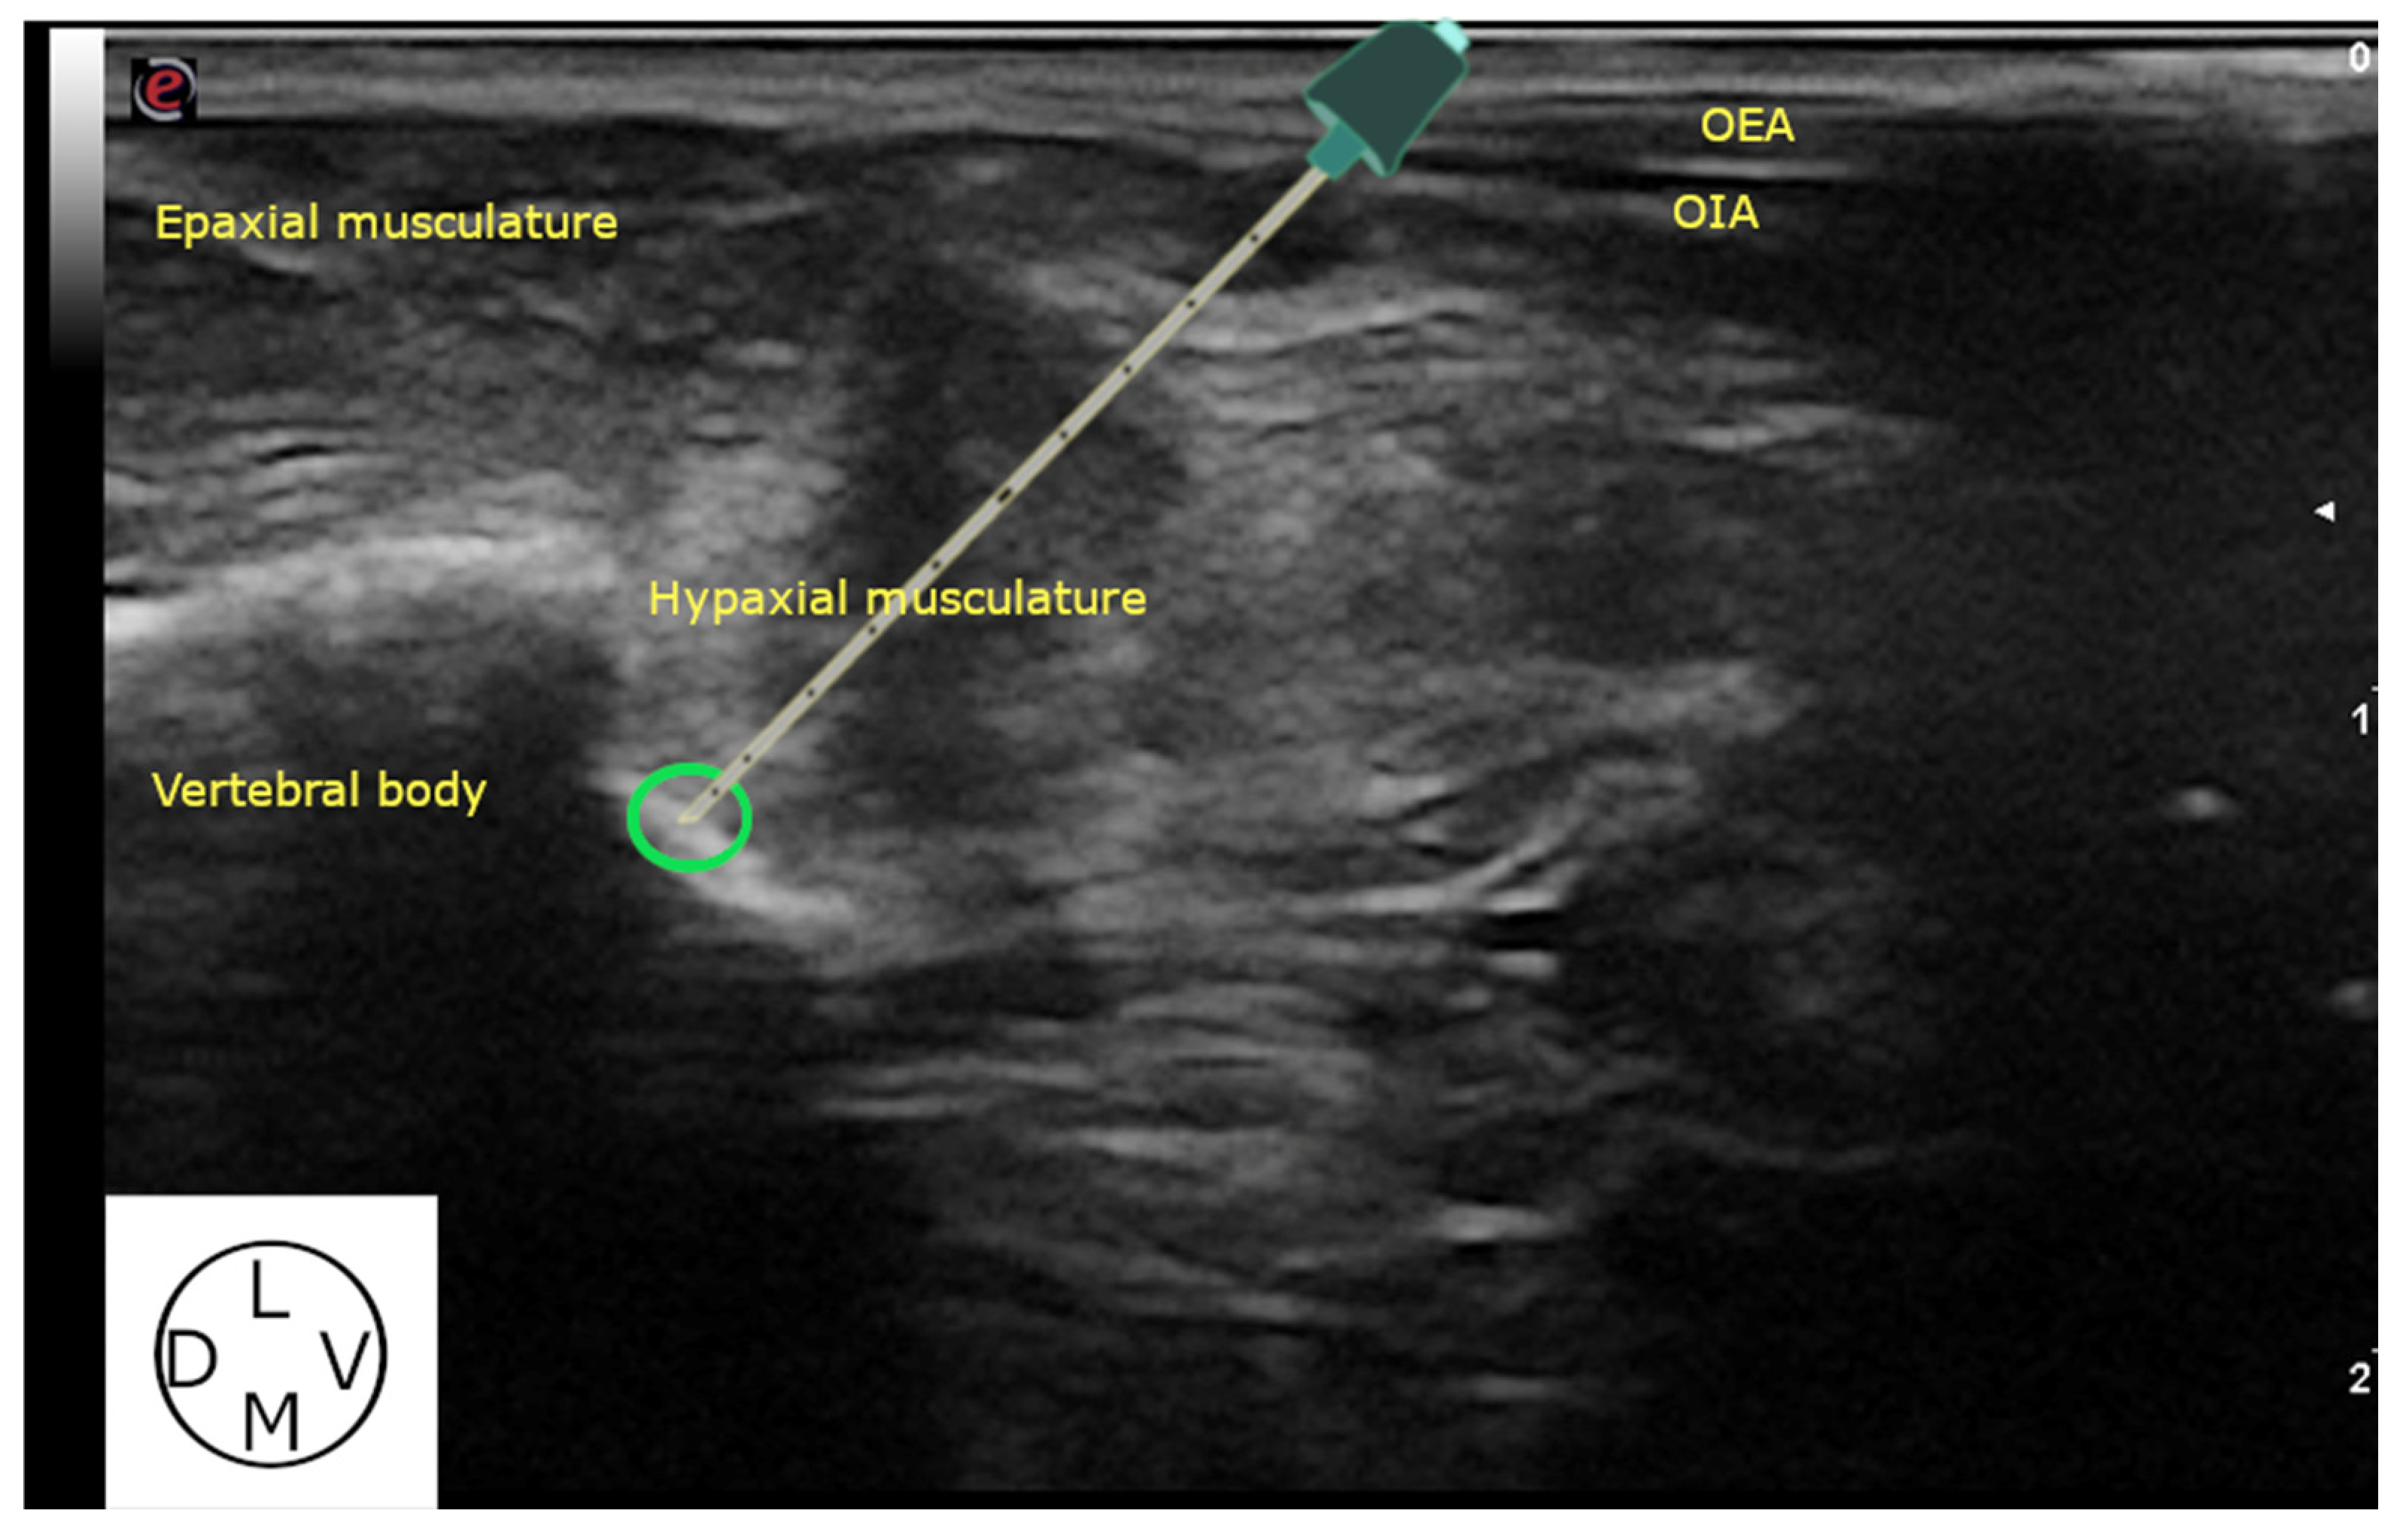

2.2.1. Ultrasound-Guided Technique

3.2.2. Ultrasound-Guided Technique